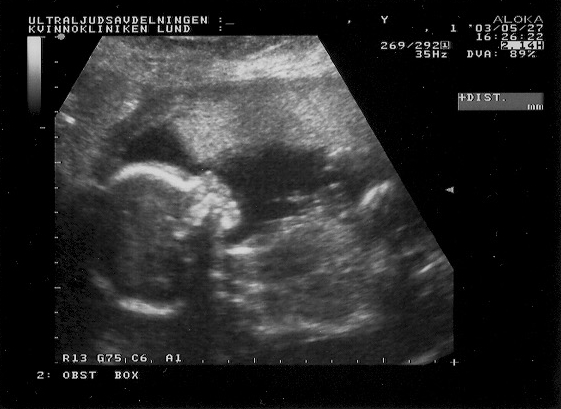

Ultra sound images from May 27, 2003.

The fetus is here 20cm tall and approx 20 weeks old.